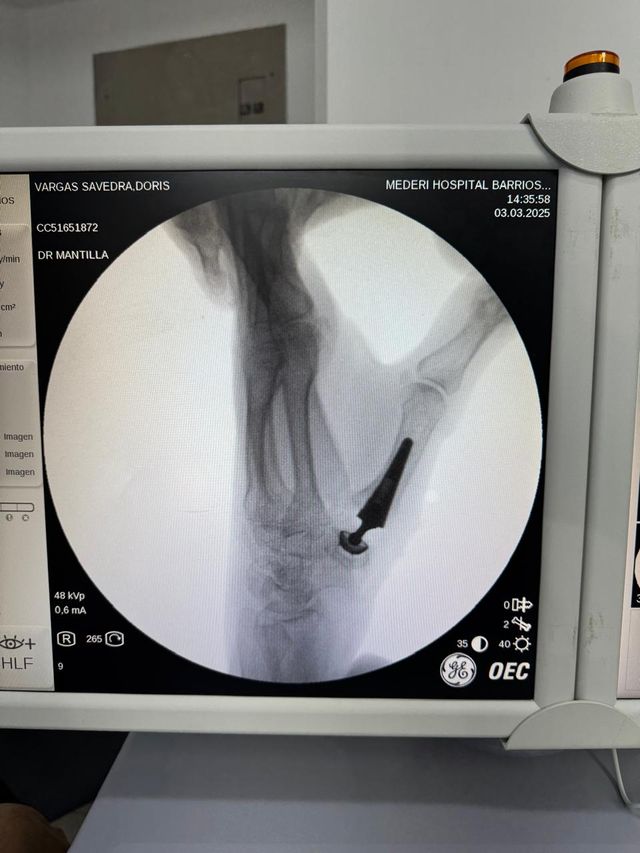

prótesis trapecio metacarpiana como solución tecnológica innovadora para dolor en base de pulgar preservando buena movilidad y función del pulgar

Hospital Universitario Mederi